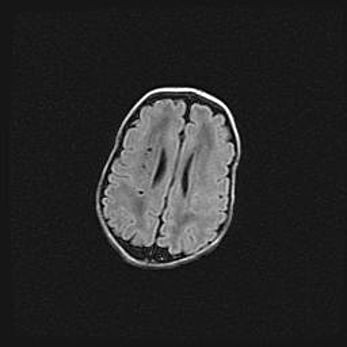

Церебральная ишемия II.

Возраст: 5 дней

Вес: 3400 г

Пол: женский

Окружность головы: 35 см

Срок гестации: 39 недель

Церебральная ишемия – это заболевание, характеризующееся недостаточностью (гипоксией) либо полным прекращением (аноксией) снабжения мозга кислородом по причине закупорки одного или нескольких сосудов. Это приводит к  что метаболическим расстройствам различной степени тяжести в тканях головного мозга, развитию коагуляционных некрозов и гибели нейронов.